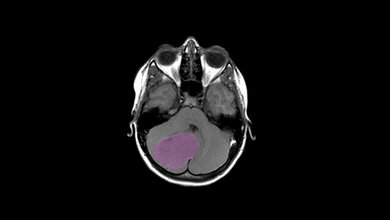

Prof. Michael Hauptmann, Professor für Biometrie und Registerforschung an der Medizinischen Hochschule Brandenburg Theodor Fontane (MHB), analysierte gemeinsam mit Forscherinnen und Forschern der Internationalen Agentur für Krebsforschung (IARC) und weiteren Partnerinstituten Daten von insgesamt 658.752 Kindern, die eine oder mehrere CT-Untersuchungen erhalten hatten. Dabei fanden sie einen statistischen Zusammenhang zwischen der Strahlendosis und dem Hirntumorrisiko. Es wird geschätzt, dass pro 10.000 Kinder, die eine Kopf-CT erhielten, ein strahleninduzierter Hirntumor innerhalb von 5-15 Jahren nach der CT zu erwarten ist.

„Computertomografische Untersuchungen, sogenannte CT, liefern wichtige diagnostische Informationen, die lebensrettend sein können. Gleichzeitig sind die Patientinnen und Patienten dabei einer viel höheren Strahlendosis ausgesetzt als bei Röntgenaufnahmen und den meisten anderen radiologischen Diagnoseverfahren. Mehrere frühere Studien deuteten bereits darauf hin, dass CT-Untersuchungen des Kopfes bei Kindern mit einem erhöhten Hirntumorrisiko verbunden sind. Genaue und solide Schätzungen des Krebsrisikos insbesondere in Abhängigkeit von der CT-Strahlendosis fehlten jedoch und werden dringend benötigt, um Strategien zur Dosisoptimierung zu entwickeln. Diese Schätzungen liefern nun die Ergebnisse unserer Studie“, erklärt Prof. Hauptmann, Statistiker und Professor an der Medizinischen Hochschule Brandenburg Theodor Fontane in Neuruppin, der die Daten analysiert hat und dabei eine statistisch signifikante lineare Dosis-Wirkungs-Beziehung für Hirntumore fand.

„Das Exzess Relative Risiko pro 100 Milligray Strahlendosis für das Gehirn betrug 1,27 (mit einem 95 % Konfidenzintervall von 0,51 bis 2,69). Dies bedeutet, dass das Hirntumorrisiko nach einer Belastung von 100 Milligray, was etwa 2-3 Kopf-CTs entspricht, um 127% höher ist als ohne Kopf-CTs. Trotz dieser starken Erhöhung ist das absolute Risiko, an einem Hirntumor zu erkranken, für einzelne Patientinnen und Patienten auch dann zwar immer noch sehr gering. Allerdings werden in Europa und anderen Ländern jährlich Millionen von Kopf-CT-Untersuchungen bei Kindern durchgeführt. Es besteht somit nach wie vor ein großer Forschungsbedarf, welche Strahlenbelastung bei welchem Organ mit welchem Risiko verbunden ist“, so Prof. Hauptmann weiter.